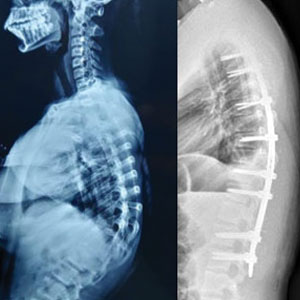

Some of the spinal corrections: